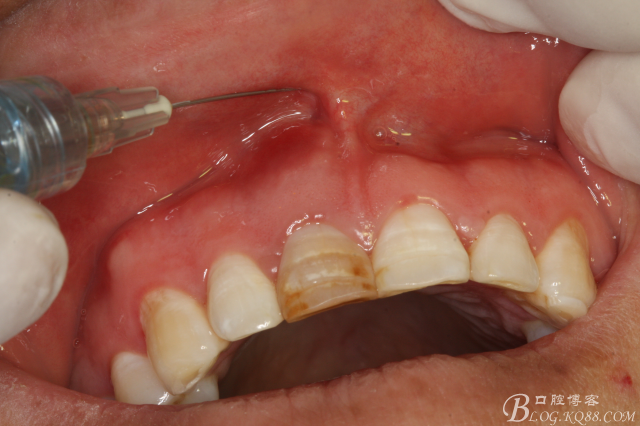

圖1.口內(nèi)像:唇側(cè)粘膜紅腫、牙冠成灰褐色

圖4,唇側(cè)、腭側(cè)局部浸潤麻醉